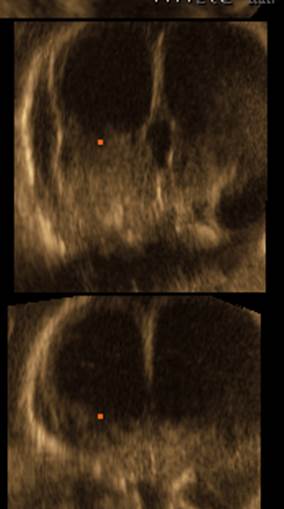

Вопрос 4

Срок 22 недели 5 дней. Вентрикуломегалия тяжелой степени. Пол плода — женский. В какой части головного мозга скрывается основной диагноз?

Трансцеребеллярный скан и 3Д режимы

Ответ на вопрос 4

- Поиск основного диагноза нужно вести в области задней черепной ямки (смотрим НАЗАД).

- Очевидно, что полушария мозжечка уменьшены в размерах (фокальная гипоплазия полушарий мозжечка), червь сформирован правильно (об этом подробно поговорим на второй лекции).

- При консультировании — обязательно предлагаем инвазивную диагностику с лабораторным исследованием молекулярного кариотипа (ХММА).